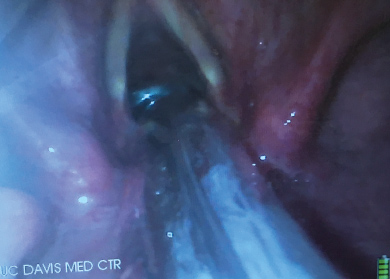

When the trachea is extremely tortuous and it has been impossible to slide a standard ETT over the FIS into the trachea, a spirally reinforced or "armored" ETT can be used. This type of ETT will follow the FIS more easily because it has less internal rigidity and therefore conforms more readily to unusual tortuous airway anatomy. The Parker flex tip endotracheal tube has also been shown to pass more easily over a fiberscope than a conventional ETT [37]. The ETT that is provided with the intubating LMA is a soft wire-reinforced silicon tube and its tip conforms readily to airway anatomy and is also excellent at sliding easily over a flexible bronchoscope (Figure 3, Figure 4 and Figure 5) [38].

Figure 3: The vocal cords are visualized with the video-laryngoscope (VL) while the flexible intubation scope (FIS) is used to steer the endotracheal tube (ETT) into the trachea.

Figure 4: Video-laryngoscope (VL) view of a flexible intubation scope (FIS) passing over the arytenoids. The FIS is ante-flexed by pushing the thumb down.

Figure 5: Video-laryngoscope (VL) view of the flexible intubation scope (FIS) having passed the vocal cords. The FIS is retroflexed by pushing the thumb up.